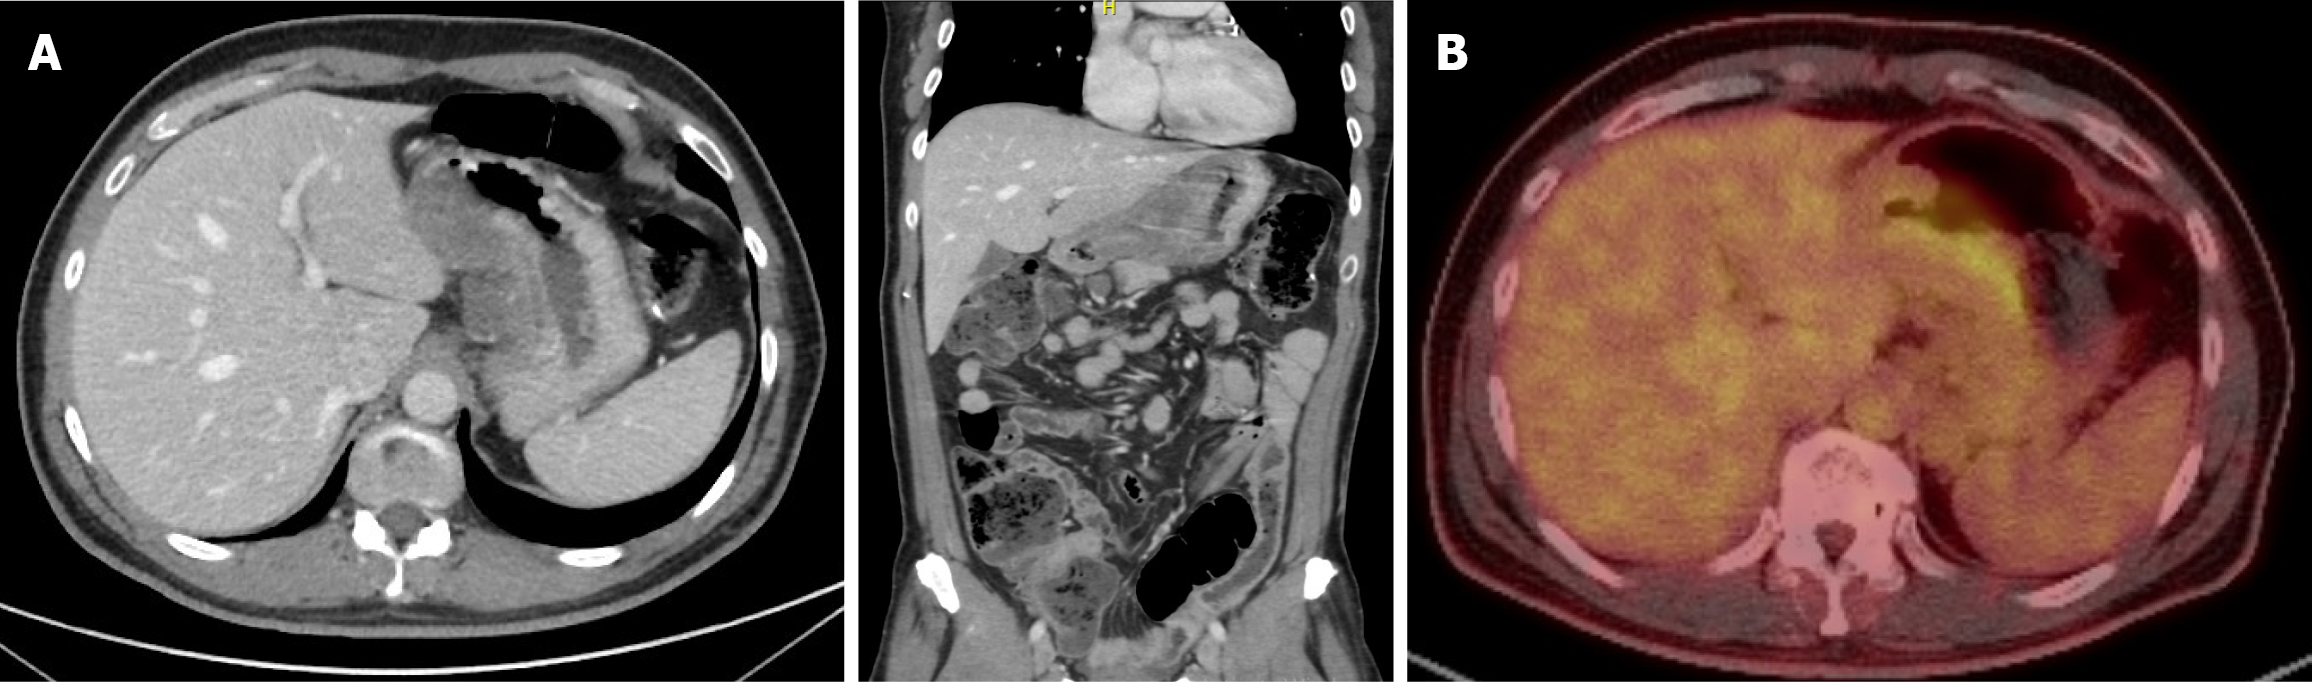

Figure 2 Post-neoadjuvant chemotherapy whole body positron emission tomography/computed tomography scan showing significant interval metabolic activity regression of the previously noted gastric lesser curvature FDG avid thickening and complete metabolic remission of the previously noted locoregional lymphadenopathy.

A: Whole body positron emission tomography/computed tomography scan post-neoadjuvant chemotherapy showing A-significant interval metabolic activity regression of the previously noted gastric lesser curvature FDG avid thickening and complete metabolic remission of the previously noted locoregional lymphadenopathy; B: New FDG uptake in an ileal bowel loop that was reported as inflammatory/infectious.